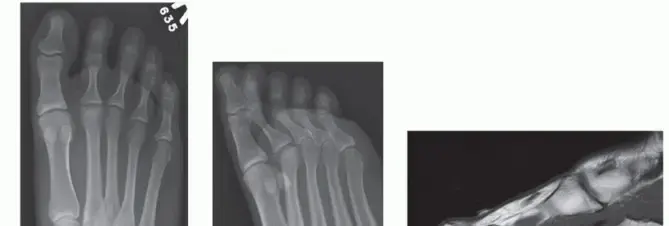

أ. الأشعة السينية (X-rays)

- تعتبر الأشعة السينية المحمولة على الوزن (Weight-bearing Foot Radiographs) هي الخطوة الأولى والأساسية لتأكيد التشخيص.

- ما الذي تكشفه: في المراحل المبكرة، قد تظهر الأشعة السينية تسطحًا طفيفًا في رأس عظم المشط. مع تقدم المرض، يمكن رؤية انهيار واضح في رأس العظم، وربما تفتت للعظم، وتغيرات في شكل المفصل.

- تصنيف سميلي (Smillie Classification): يستخدم الدكتور هطيف هذا النظام العالمي لتصنيف شدة داء فرايبرغ إلى مراحل (من 1 إلى 5)، مما يساعد في توجيه خيارات العلاج. على سبيل المثال، المرحلة 1 تشير إلى تسطح بسيط، بينما المرحلة 5 تعني انهيارًا كاملاً لرأس العظم وتدمير المفصل.

- خبرة الدكتور هطيف: في كثير من الحالات التي يراها الدكتور هطيف، يكون المرضى قد وصلوا إلى مراحل متوسطة، حيث تظهر الأشعة السينية انهيارًا في الجزء العلوي (الظهري) من رأس عظم المشط مع بقاء الجزء السفلي (الأخمصي) سليمًا نسبيًا.